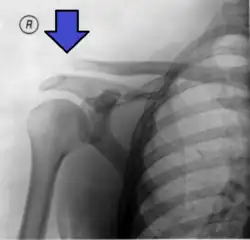

An Xray showing a separated shoulder. Notice the separation between the end of the collarbone and the scapula.

X-ray indicates a separated shoulder when the acromioclavicular joint space is widened (it is normally 5 to 8 mm).[9]